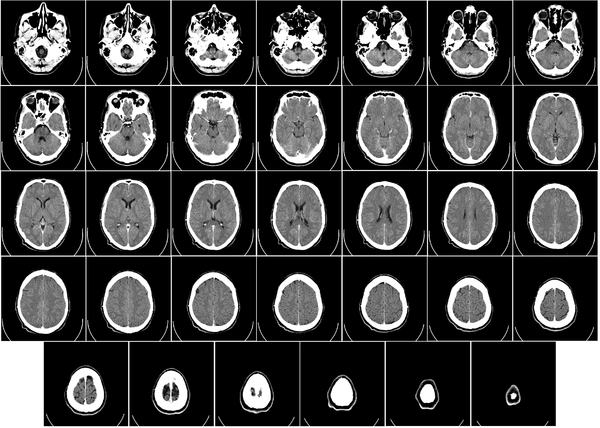

معرض الصور

يوضح ماسح التصوير المقطعي الحاسوبي بدون غلافه كيف يعمل؛ داخل الجهاز الذي يكشف عن داخلك |